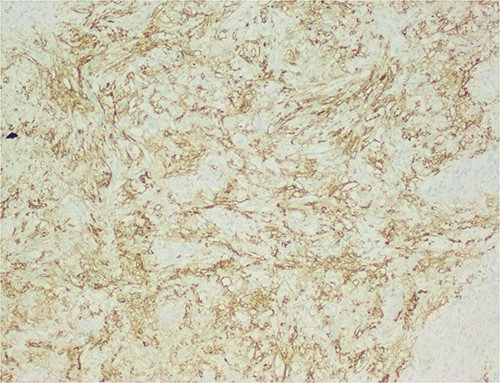

The histological evaluation of the surgical specimen revealed a storiform fusiform cell neoplasm with expansive borders, areas of a myopericytomatous pattern, and the presence of rhabdoid cells (Fig. 4). The neoplastic cells, spindled to oval, with eosinophilic and granular cytoplasm and with mild nuclear atypia, were organized in small bundles (Fig. 5). Anomalous arterial structures were observed. Neither necrosis nor mitotic figures were identified. The immunohistochemical study revealed immunoreactivity of neoplastic cells for SMA, HHF35 (Fig. 6) and HMB45 (Fig. 7), Calponin, S100 and CD31. The margins did not intersect the neoplasm. Thus, contrary to the preoperative diagnosis of hepatocellular carcinoma, the morphological aspects and the immunohistochemical profile favored the diagnosis of epithelioid angiomyolipoma.

The neoplastic cells are organized in small bundles. The cells are spindled to oval, with eosinophilic and granular cytoplasm and with mild nuclear atypia.